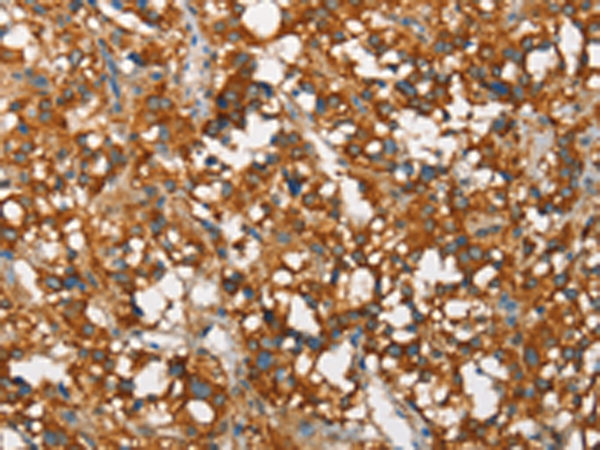

分类: 科研抗体货号: P11552别名: 5-HT3B应用: IHC反应种属: Human